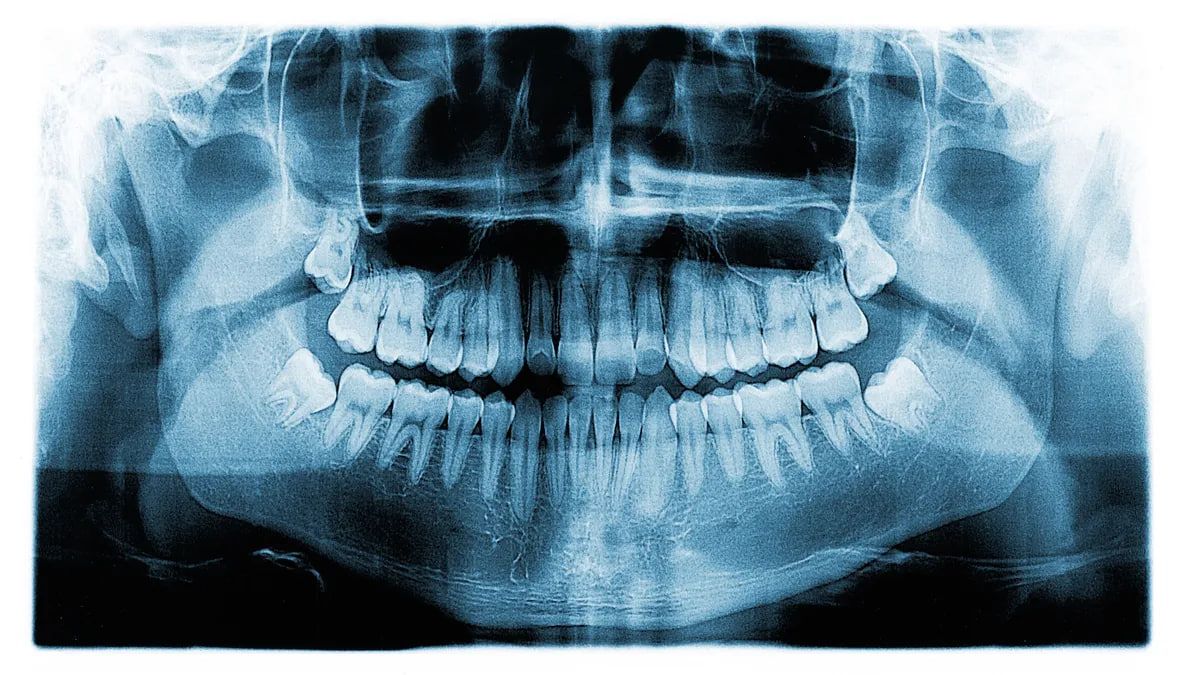

Когда 14-летний мальчик пришел на плановое стоматологическое освидетельствование, стоматологи обнаружили, что на его первом левом премоляре было две коронки. Согласно отчету о случае, у него не было никаких симптомов, связанных с зубом, и он не нуждался в каком-либо лечении. Геминация зубов, широко известная как двойные зубы, является нарушением развития формы зуба, возникающей в результате неудачной попытки разделения одного зачатка зуба.